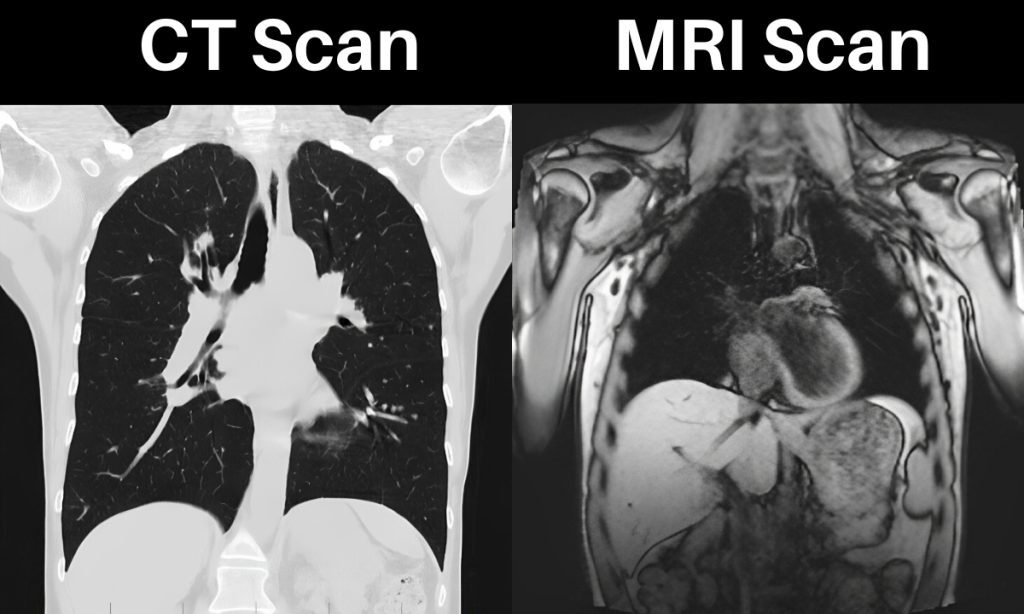

سی تی اسکن یا CT Scan یکی از روشهای پیشرفته تصویربرداری پزشکی است که با استفاده از اشعه ایکس و پردازش کامپیوتری تصاویر مقطعی و دقیق از بدن تولید میکند. این تصاویر به پزشکان کمک میکنند تا ساختارهای داخلی بدن مانند استخوانها، ریهها، عروق و اعضای داخلی را از زوایای مختلف بررسی کنند. یکی از مهمترین مزایای سی تی اسکن، سرعت بالای آن است؛ به همین دلیل در شرایط اورژانسی مانند تصادفات یا خونریزیهای داخلی، معمولاً اولویت انتخاب پزشکان است. کاربردها و مزایای سی تی اسکن:

Hاین روش در بهترین مراکز سی تی اسکن تهران با اشعه ایکس انجام میشود و تکرار مکرر آن محدود است. این روش در بررسی بافتهای نرم مانند عضلات و برخی ارگانها دقت کمتری دارد. درک فرق سی تی اسکن و ام آر آی به پزشکان و بیماران کمک میکند تا بدانند چه زمانی استفاده از این روش سریع و کاربردی است.

ام آر آی چیست و چه کاربردی دارد؟

ام آر آی یا MRI یک روش تصویربرداری پیشرفته است که با استفاده از میدان مغناطیسی قوی و امواج رادیویی تصاویر سهبعدی و با جزئیات بالا از بدن ایجاد میکند. برخلاف سی تی اسکن، ام آر آی اشعه ایکس ندارد و برای اکثر بیماران کاملاً ایمن است. این ویژگی باعث شده تا ام آر آی برای بررسی طولانیمدت یا تکراری بیماران بسیار مناسب باشد، به ویژه زمانی که نیاز به مشاهده دقیق بافتهای نرم وجود دارد. کاربردها و مزایای ام آر آی:

ام آر آی زمان طولانیتری نسبت به سی تی اسکن دارد و هزینه بالاتری دارد. افرادی که ایمپلنت فلزی یا دستگاه ضربانساز قلب دارند، ممکن است نتوانند از آن استفاده کنند. آشنایی با فرق سی تی اسکن و ام آر آی کمک میکند بیماران بدانند چه زمانی نیاز به تصویربرداری با جزئیات بالای بافت نرم دارند و چه زمانی روش سریعتر و سادهتر مناسب است.

تفاوت سی تی اسکن و ام آر آی در کاربردهای پزشکی

هر روش تصویربرداری مزایا و کاربردهای خاص خود را دارد و شناخت فرق سی تی اسکن و ام آر آی به پزشکان و بیماران کمک میکند تا تصمیم بهتری برای تشخیص و درمان بگیرند. سی تی اسکن و ام آر آی هر کدام در حوزه خاصی عملکرد بهینه دارند و بسته به نیاز بیمار انتخاب میشوند.

کاربردهای سی تی اسکن

سی تی اسکن به دلیل سرعت بالا و دقت در بررسی ساختارهای سخت بدن، در شرایط اورژانسی و تشخیص آسیبهای استخوانی بسیار مفید است. مهمترین کاربردهای آن شامل موارد زیر است:

کاربردهای ام آر آی

ام آر آی دقت بسیار بالایی در بافت نرم بدن دارد و برای مشاهده جزئیات دقیق ارگانها و بافتهای نرم مناسب است. کاربردهای آن شامل موارد زیر است: